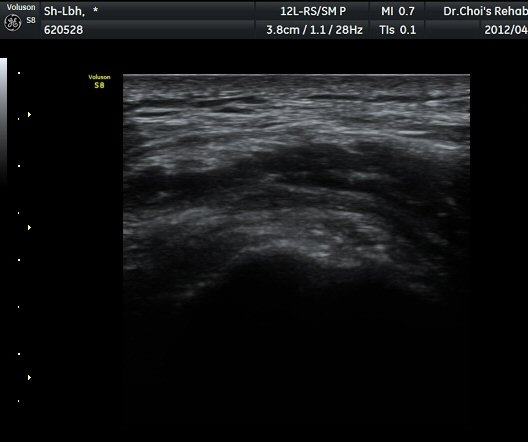

ÃÊÀ½ÆÄ °Ë»ç

´ëÀüÀÚ(gtreater trochanter) ¾ÕºÎºÐ Ⱦ´Ü¸é °Ë»ç¿¡¼­ ´ëÀüÀÚ Ç¥Ãþ¿¡ ¼ÒµÐ±ÙÀÌ °í¿¡ÄÚ ¼¶À¯¾ç ¸ð¾çÀ¸·Î °üÂûµÇ°í ¼ÒµÐ±Ù°ú Àå°æÀÎ´ë »çÀÌ¿¡ ¾à 2mm µÎ²²ÀÇ Á¤¾×³¶ ºÎÁ¾ÀÌ °üÂûµÈ´Ù(±×¸² 1, ³ë¶õ»ö È­»ìÇ¥) . ŽÃËÀÚ¸¦ µÚÂÊÀ¸·Î À̵¿ÇÏ¿© Áߵб٠ÈûÁÙÀÌ °üÂûµÇ°í Áߵб٠ÈûÁÙ ºÎÂøºÎ ÀϺο¡ ¹«¿¡ÄÚ ¿¬°á¼º ¼Ò½ÇÀÌ °üÂûµÇ°í ±× Ç¥Ãþ¿¡µµ Á¡¾×³¶ÀÇ ºÎÁ¾ÀÌ °üÂûµÈ´Ù(±×¸² 2). ȯÀÚÀÇ µÚÂÊ¿¡¼­ ÃÊÀ½ÆÄ À¯µµÇÏ ÁÖ»çÄ¡·á¸¦ À§ÇØ ºñ½ºµëÇÑ È¾´Ü¸é°Ë»ç¿¡¼­ ´ëµÐ±Ù